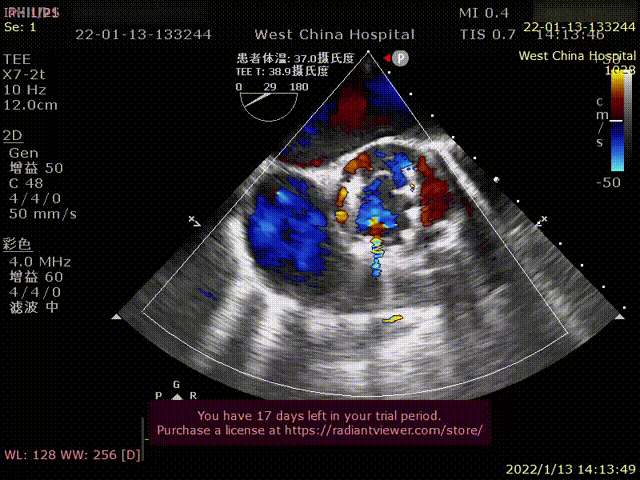

患者为69岁男性,因“活动后胸闷,气紧十年余,加重1月”主诉入院。术前超声提示:左心明显增大,LVDD 82mm,LVEF 26%,主动脉瓣重度狭窄伴重度反流。术后即刻主动脉瓣大量反流消失,超声显示LVDD 65mm,左心较术前显著缩小。

术后超声1

术后超声2